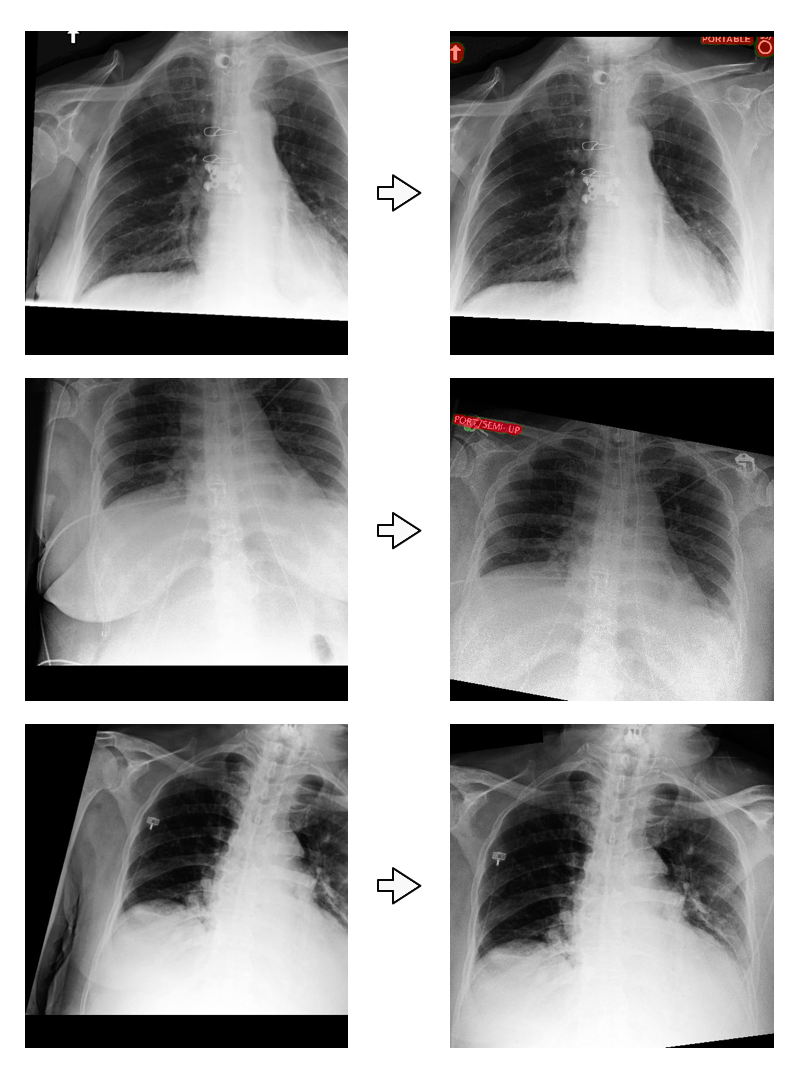

Refer to caption

Figure 3: Example input radiographs (left) with output alignment (right) and annotation masks (red).

After the model was trained, it was run on the full cohort of 501,242 frontal chest films (Figure 3) for future evaluation purposes. No further filtering (e.g. segmentation size threshold of annotation objects) was performed on the model output.